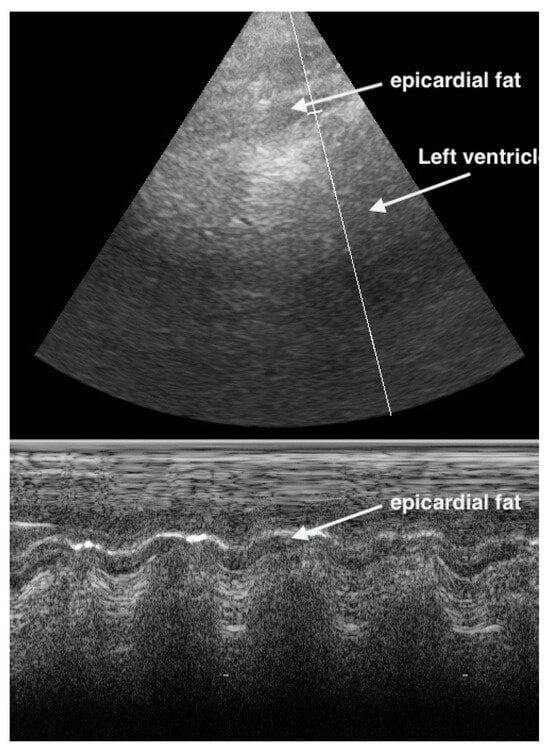

M-Mode can help to differentiate between pericardial effusion and fat. Pericardial effusion undergoes a fluctuation during heart movement and so shows a hypoechoic band which moves in thickness. In contrast, the hypoechoic band of fat does not change in thickness (Figure 11 and Figure 12).

Figure 11.

In the apical 4CV (Chambers almost not to see), in the apex is a broad hypoechoic band which has always the same size. 4CV = Four Chamber view.

Figure 12.

In the parasternal long-axis view, the hypoechoic band of the pericardial effusion varying in size during heart contraction (undulating).